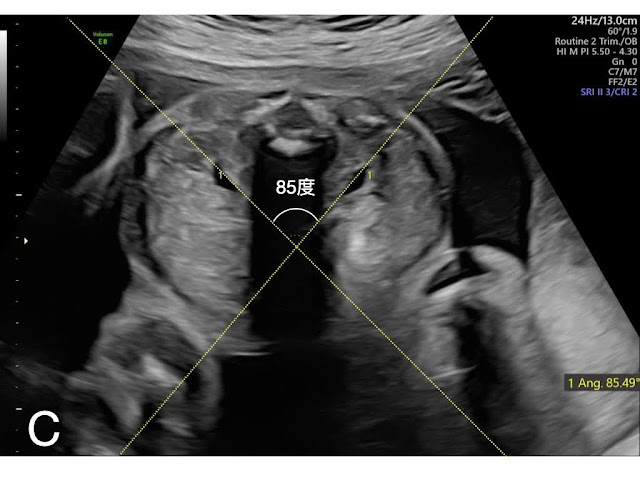

馬蹄腎易因轉位異常(malrotation)致使腎盂角度往前往內偏移(anteromedial orientation),腎盂寬度也往往較一般為大。J Y Cho 等人即運用此觀念,在西元2005年發表在《Ultrasound in Obstetrics & Gynecology》中的 〈Prenatal diagnosis of horseshoe kidney by measurement of the renal pelvic angle 〉 一文中,提到產前超音波檢查可藉由測量雙側腎臟腎盂連線的交角,得以產前診斷馬蹄腎。

診斷要點如下:取得胎兒呈俯臥姿態(prone position) 時軸向 (axial view) 下的腎臟平面,分別畫出腎盂長軸的延長線,計算雙線間的夾角,即為腎臟腎盂夾角 (Renal pelvic angle)。文章中所納入統計的胎兒,正常腎臟的腎臟腎盂夾角平均角度,在第二孕期及第三孕期,分別為172度及161度;而馬蹄腎組,則是116度及110度,兩組角度上的差異具顯著統計意義。筆者提出,若用「腎臟腎盂夾角角度小於140度」為產前馬蹄腎診斷標準,無論敏感度、特異性、正確性,皆為百分之百,圖二即為台兒診所利用此標準產前診斷的馬蹄腎與正常腎臟的圖示。若希冀在腎臟冠狀切面下(coronal view)辨識出峽部(isthmus)的位置,第三孕期優於第二孕期,或是可考慮安排胎兒磁振造影。

圖二:(C)馬蹄腎「腎臟腎盂夾角」角度測量實例(台兒診所製作)